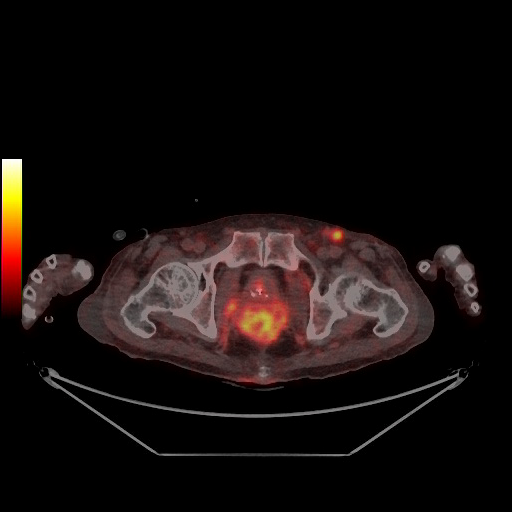

첫째, 대장암은 환자가 고령이라도 적극적인 수술이 권고된다. 대장암은 원격전이가 일어난 4기라도 수술을 통해 완치를 기대할 수 있는 거의 유일한 위장관계 악성종양이다. 수술을 통해 대장암의 근본적 치료는 물론 합병증을 최소화할 수 있다. 진단 후 사망에 이르는 기간이 긴 데다 다발성 전이 등 질환의 악화보다 장폐색, 장천공, 출혈 등 동반되는 합병증에 의한 사망 위험률이 높기 때문이다. 요즘은 70대가 넘은 대장암 환자도 평균 기대여명이 10년 이상 되는 만큼 병기와 관계없이 적극적인 치료를 고려한다. 고대구로병원에서 2015~2022년 80세 이상의 전이성 대장암 환자를 분석한 결과 약 68.1%에서 간, 폐 등 전이 병소의 동반 절제수술이 가능했다. 80세 미만 환자들의 치료성적과 비교해도 차이가 크지 않다. 일부 환자는 3회 이상의 절제수술과 항암화학요법을 통해 완치에 이르기도 했다.